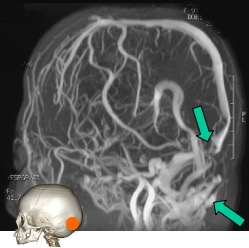

l’absorption veineux dépend donc de la pression veineuse ; en cas d’HTIC, la compression des sinus veineux et le gonflement des villosités arachnoïdiennes en leur sein peut compromettre le drainage du LCS et être à l’origine d’un cercle vicieux

le secteur veineux

un fois le liquide revenu dans le compartiment vasculaire, il peut être sous pression si les veines sont obstruées, et donc la pression peut retentir en amont et compromettre la résorption, entraînant une hyperpression.